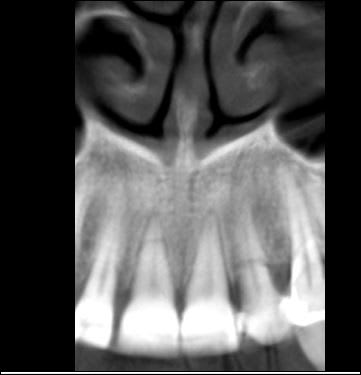

Je le vois en décembre 15j après le trauma pour faire le bilan. Puis un collage /contention sur 22 fracturée et cone beam. Brossage compliqué car grosses douleurs

le petit bonus la fracture de l'apex de 11 jusqu'ici passée inaperçue vu les douleurs de l'autre côté.